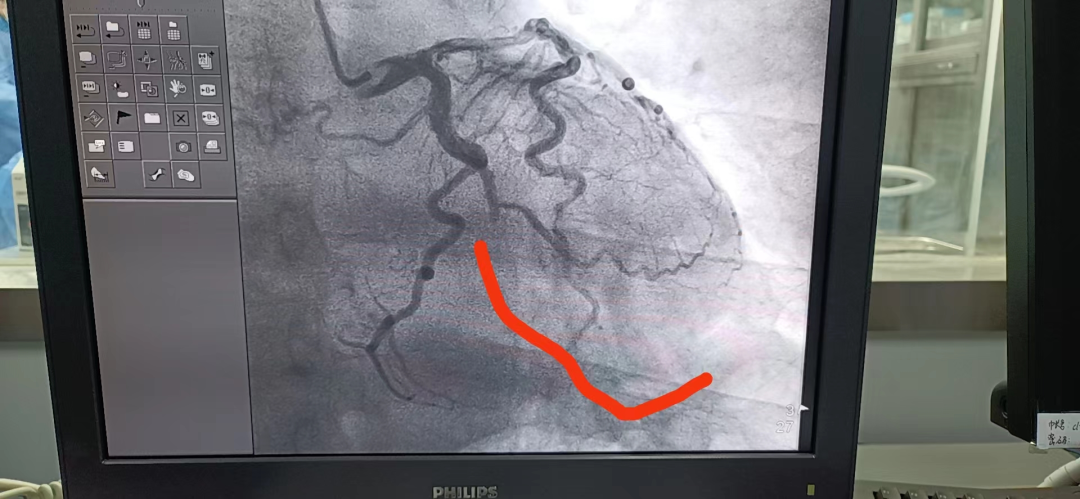

心血管病

張如幸——

科專家,副主任醫(yī)師

心血管病科專家張如幸